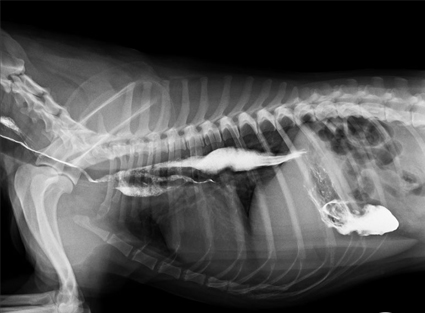

Radiología Torácica

- Evaluación de enfermedades pulmonares

- Diagnóstico de infecciones respiratorias

- Identificación de masas o tumores

- Evaluación cardíaca básica